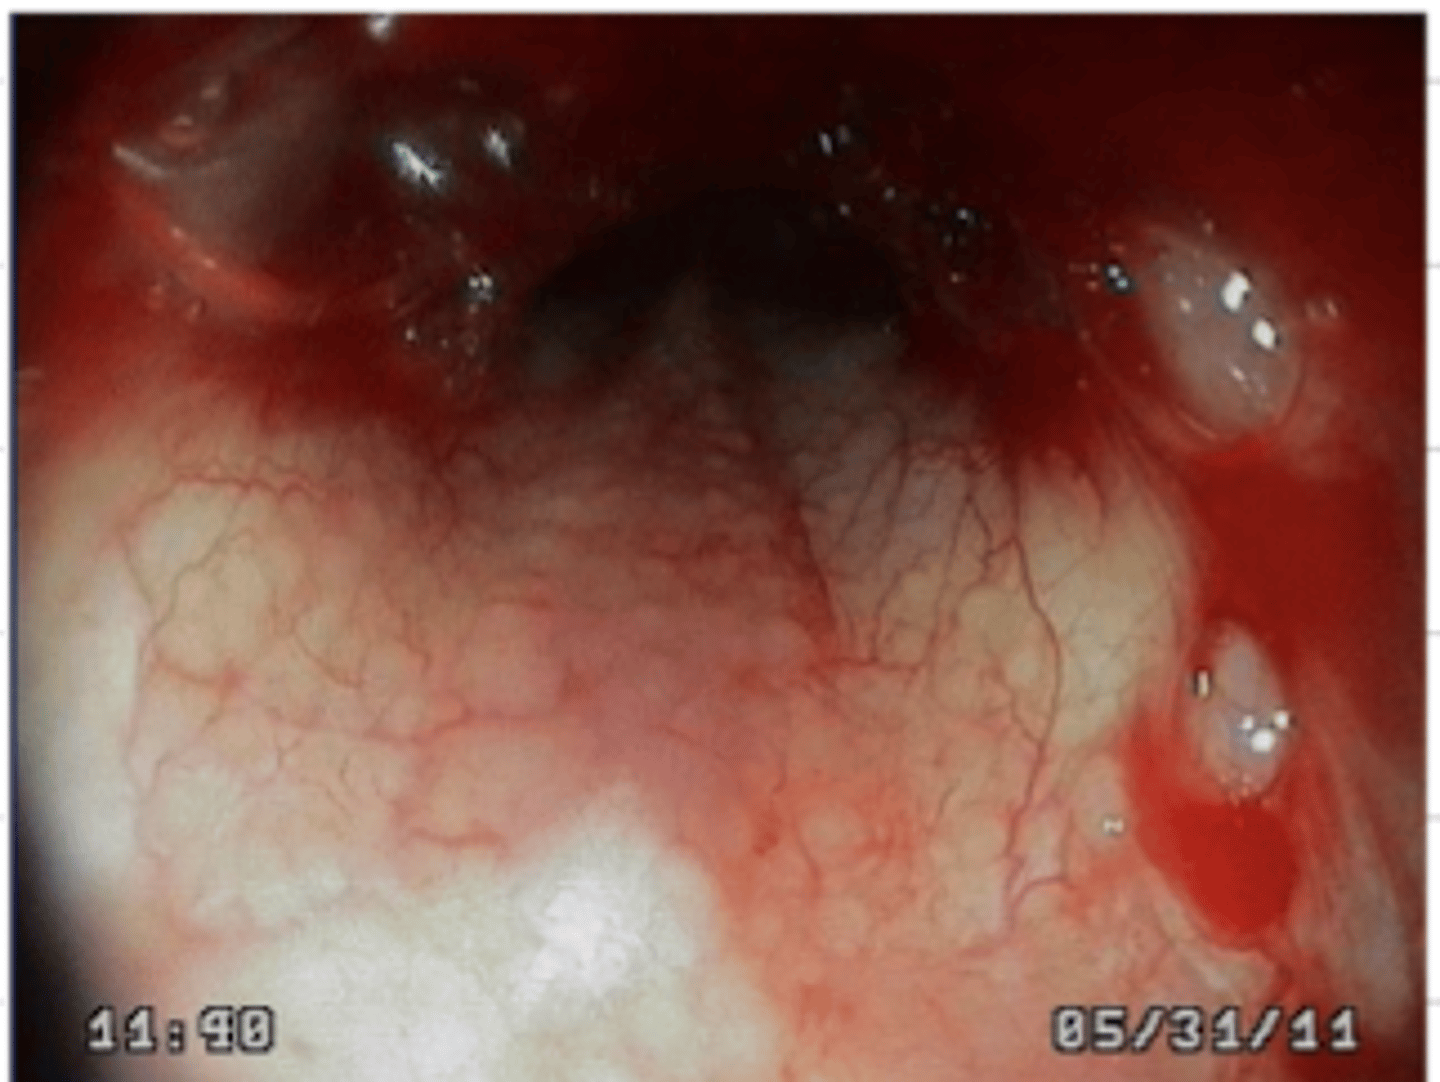

gastritis

stomach endoscopy. what disorder do we see here?